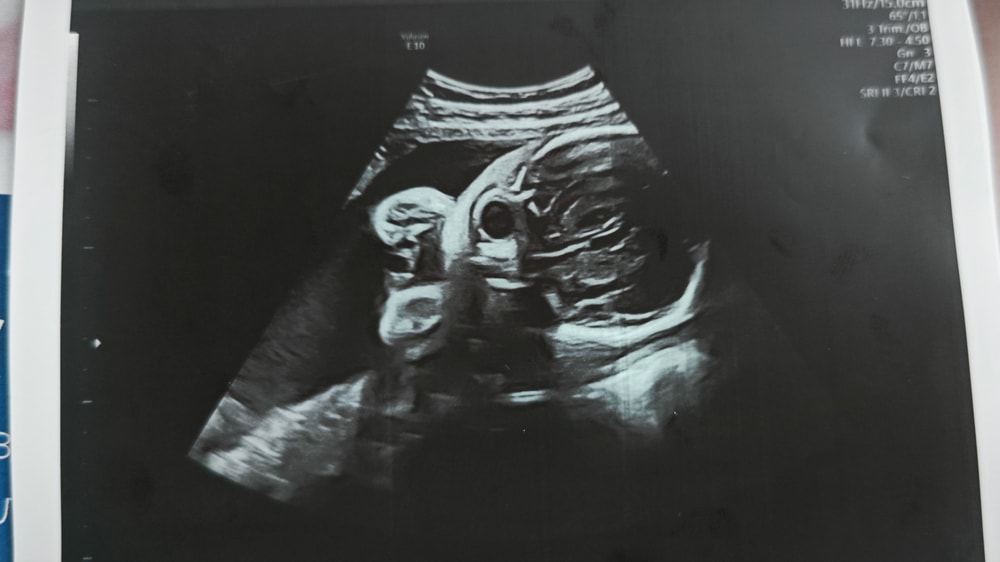

Фото с УЗИ 28 недель

Сходила в частную клинику на УЗИ в 28 недель, сказали, что всё хорошо ттт, и дали фото. И вот когда я уже вышла с клиники и увидела фото, я вообще ничего не поняла. Это вроде голова, но вообще непонятно что где и выглядит жутковато...

Анастасия , ну а что вы хотели от 2d узи? У вас все ок, видны глазницы. Лобные доли, нос. Сходите на цветное 3d, там черты лица увидите.